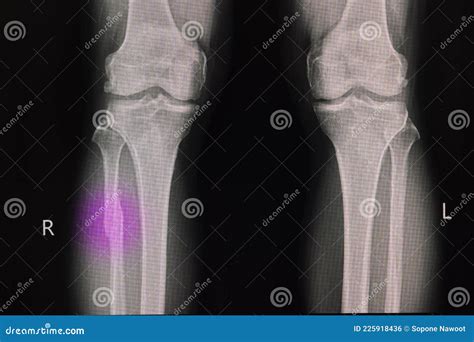

Diagnosis of Proximal Fibula Fracture

Diagnosing a Proximal Fibula Fracture involves a combination of physical examination and imaging tests. The diagnostic process typically includes:

• Physical examination: A healthcare provider will assess the injured area for pain, swelling, and deformity.

• X-rays: Imaging tests to visualize the bone and determine the location and severity of the fracture.

• CT scans or MRI: In some cases, more detailed imaging may be required to assess the extent of the injury and plan treatment.